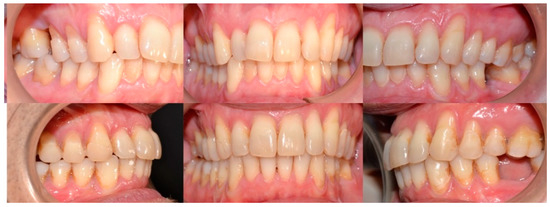

2.3.1. Example—Anterior Open-bite